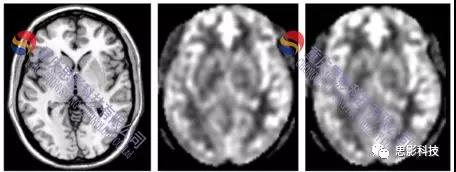

思影科技動脈自旋標記(ASL)灌注磁共振成像數(shù)據(jù)處理業(yè)務

ASL數(shù)據(jù)處理業(yè)務:

1.數(shù)據(jù)預處理:

具體包括:數(shù)據(jù)轉換、圖像復位、頭動校正、配準、平滑、去除顱外體素、計算CBF等。